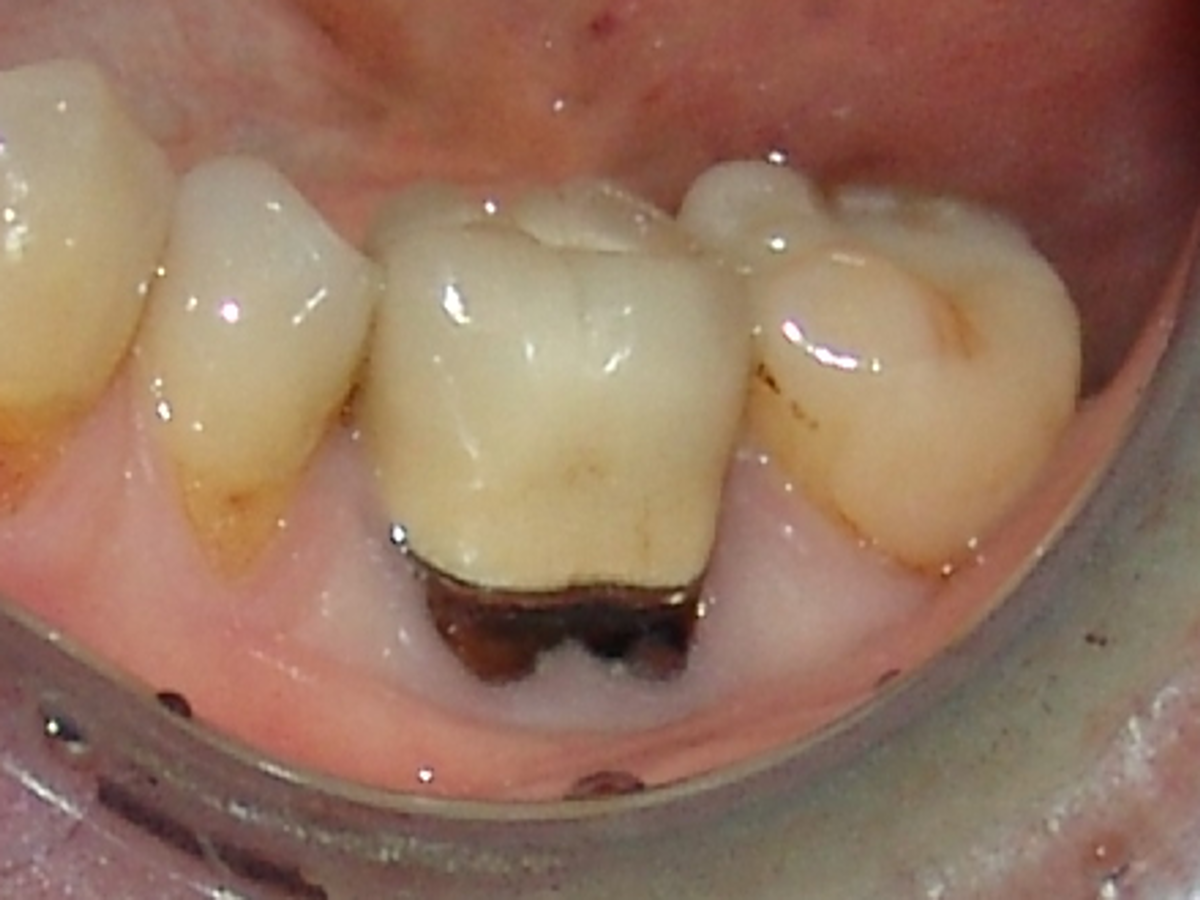

Sofern der Zahnhals freiliegt sind die Zähne dunkel verfärbt (Schwarz ist die Farbe des Todes). Bei diesem Zahn ist auch noch eine Silberkrone zu erkennen, was unter Umständen die Giftigkeit des Zahnes noch weiter erhöht.

Bei diesem überkronten wurzelbehandelten Zahn ist der dunkle abgestorbene Teil wieder gut zu erkennen. Aber hier soll noch etwas hervorgehoben werden. Das Zahnfleisch welches den Zahn umrandet ist deutlich gräulich sulzig verändert. Diese ist häufig auf die Einwirkung der Bakterien und Toxinen zurückzuführen.